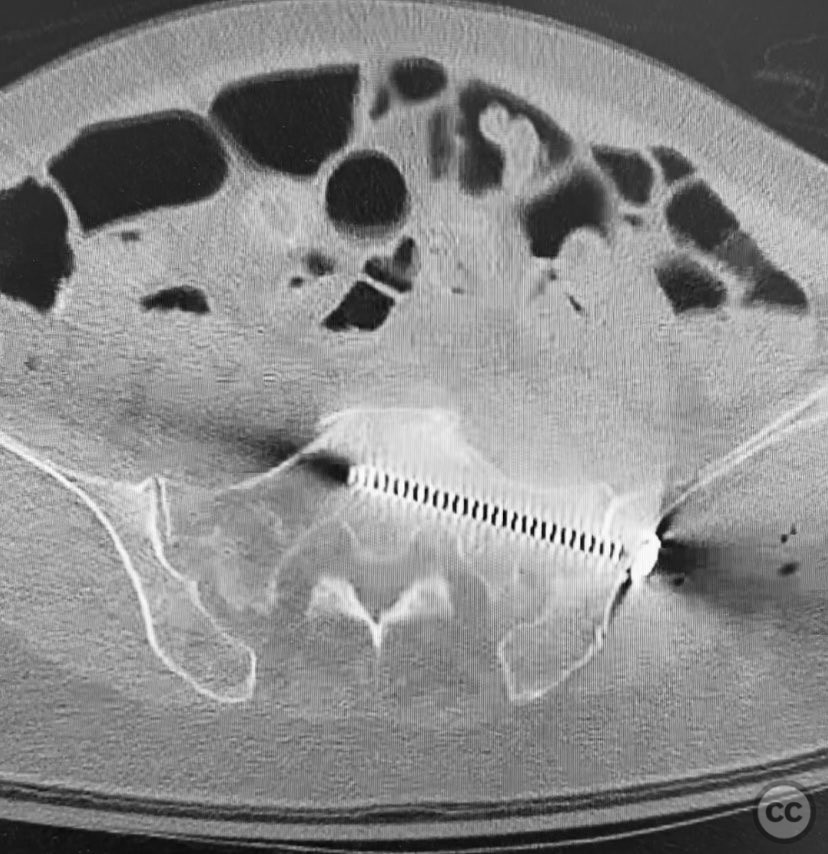

Clinical and radiological findings:  A 74-year-old female presented following a fall from standing height, unable to mobilize due to severe pelvic pain (9/10). Examination under anesthesia with fluoroscopic assessment (AP and inlet views) demonstrated instability and displacement of the pelvic ring with minimal manual compression at the iliac crests. Imaging revealed left-sided posterior iliac/sacral and pubic ramus fractures consistent with an AO/OTA 61-B2 (lateral compression type) pelvic ring injury. No neurovascular deficits were noted.

Planning remarks:  The preoperative plan involved closed reduction of the pelvic ring under fluoroscopic guidance, followed by percutaneous screw fixation of the left posterior iliac/sacral region and the ipsilateral pubic ramus. Detailed preoperative CT imaging was used to plan safe osseous corridors for screw placement, correlating with intraoperative fluoroscopic landmarks.

Anatomical surgical approach:  Percutaneous technique was employed. Small stab incisions were made over the lateral aspect of the pelvis. Under continuous fluoroscopic guidance, guidewires were advanced through the ilium into the sacrum (iliosacral region) and through the superior pubic ramus. Cannulated screws were then inserted over the guidewires, ensuring extra-articular and intraosseous positioning within the safe bone corridors as determined by preoperative CT analysis.

Orthopaedic implants used:   Cannulated iliosacral screw, cannulated pubic ramus screw